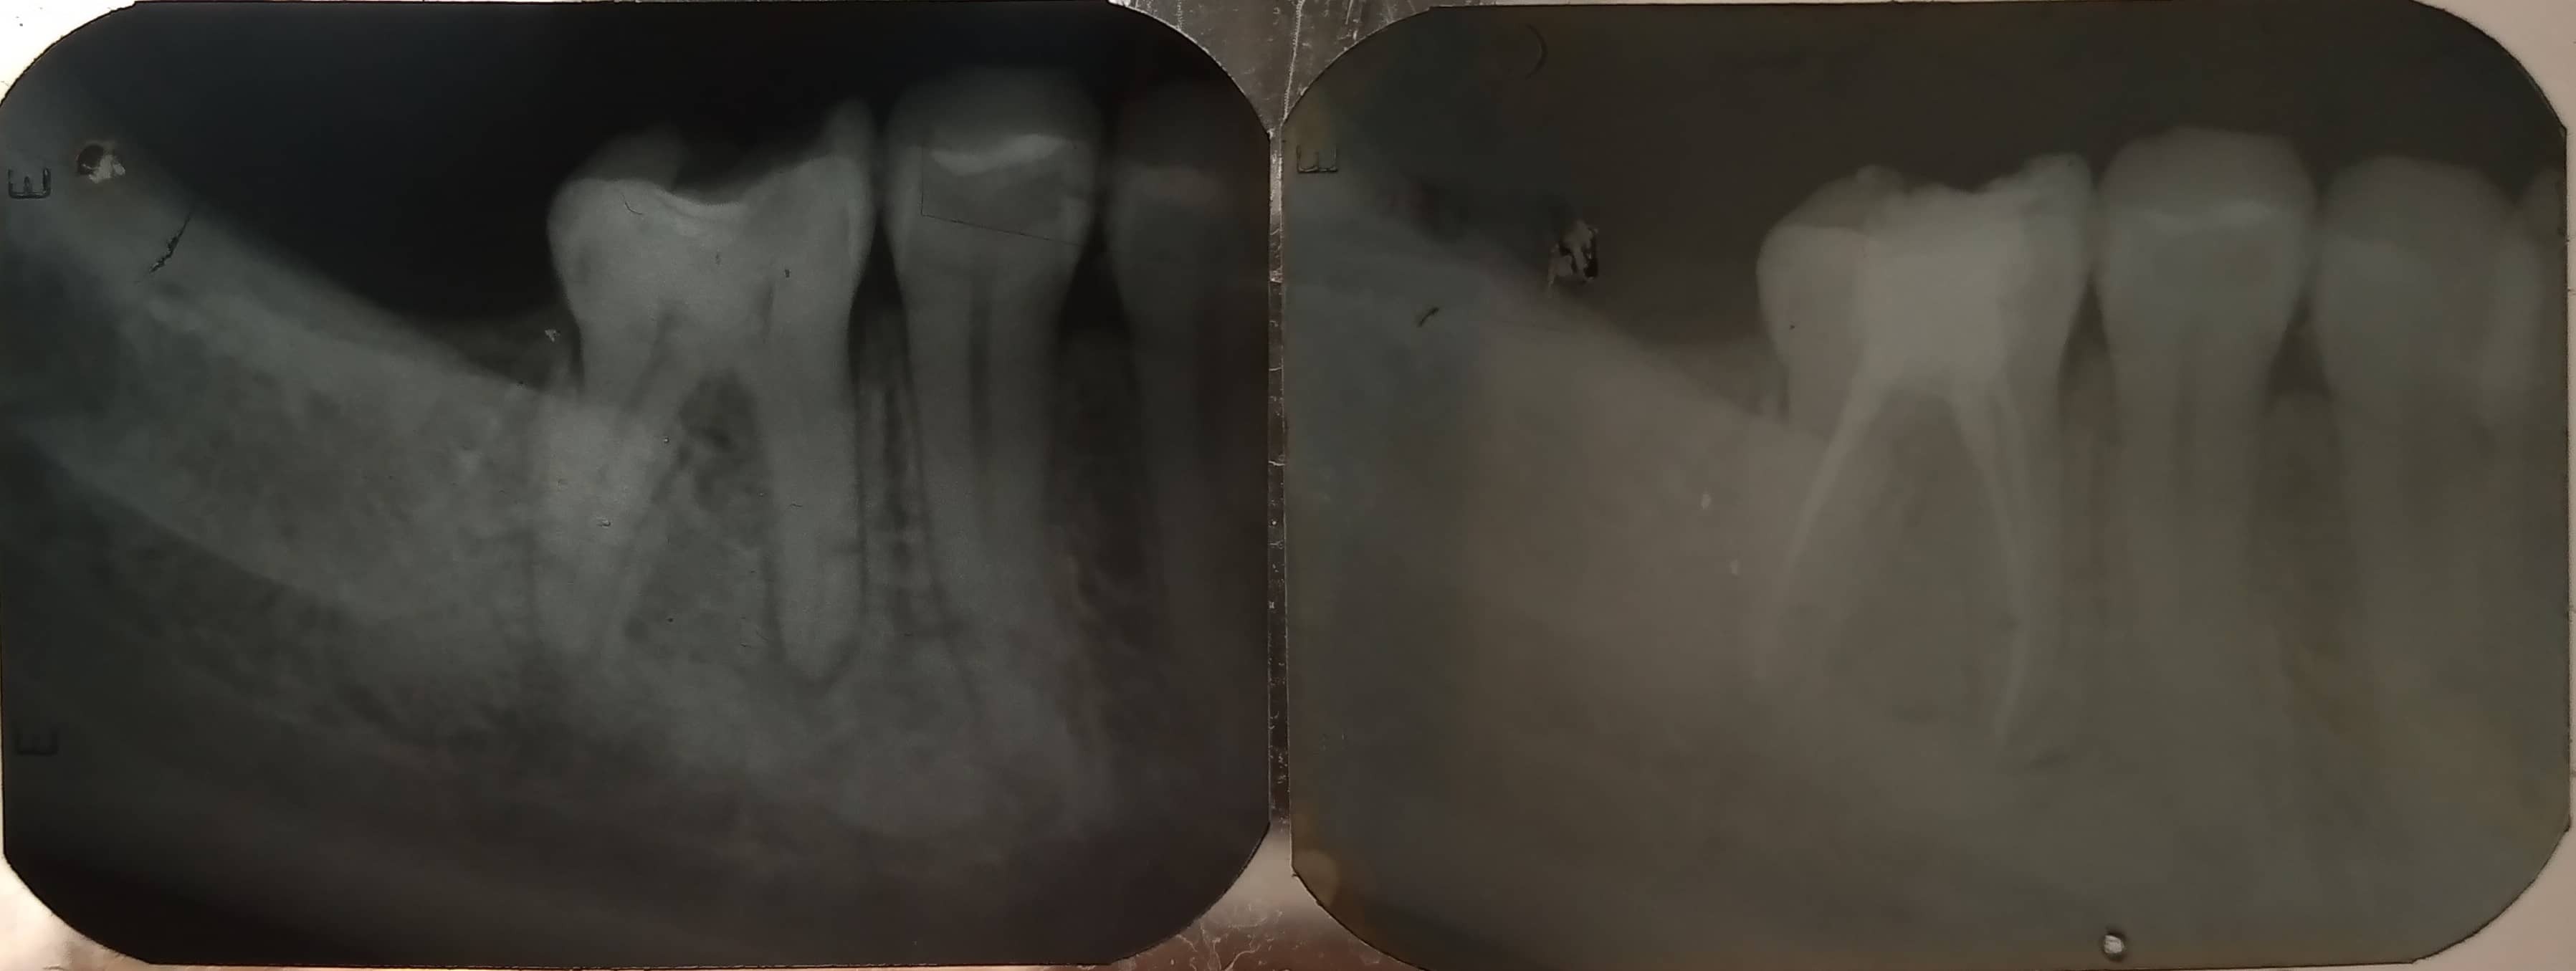

En ocasiones es requerido desvitalizar la pieza dental y asegurar su conservación, a partir del extracción del nervio, evitando así, dolores e infecciones, que afectan la salud bucal.

Este tratamiento que incluye una complejidad y atención implica la microcirugía interna del diente.